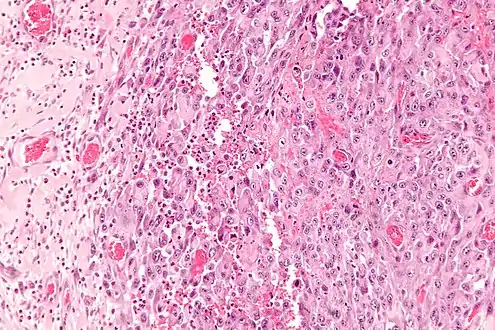

| Micrograph of an epithelioid sarcoma. H&E stain. | |

Histologically, epithelioid sarcoma forms nodules with central necrosis surrounded by bland, polygonal cells with eosinophilic cytoplasm and peripheral spindling.[3] Epithelioid sarcomas typically express vimentin, cytokeratins, epithelial membrane antigen, and CD34, whereas they are usually negative for S100, desmin, and FLI1 (FLI-1).[3] They typically stain positive for CA125.[4]

High mag.